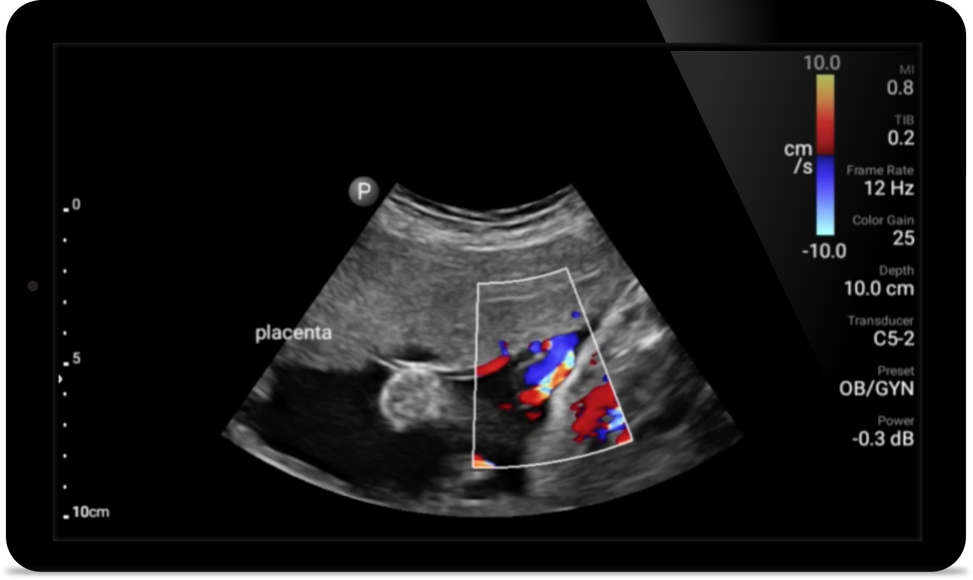

Lumify C5-2 broadband curved array transducer

• 5 to 2 MHz extended operating frequency range • 50mm radius of curvature • 2D, color Doppler, M-mode, advanced XRES and multivariate harmonic imaging, SonoCT • High-resolution imaging for deeper applications: abdominal, gall bladder, OB/GYN and lung imaging preset optimizations • Center line marker • USB-C transducer with replaceable cable